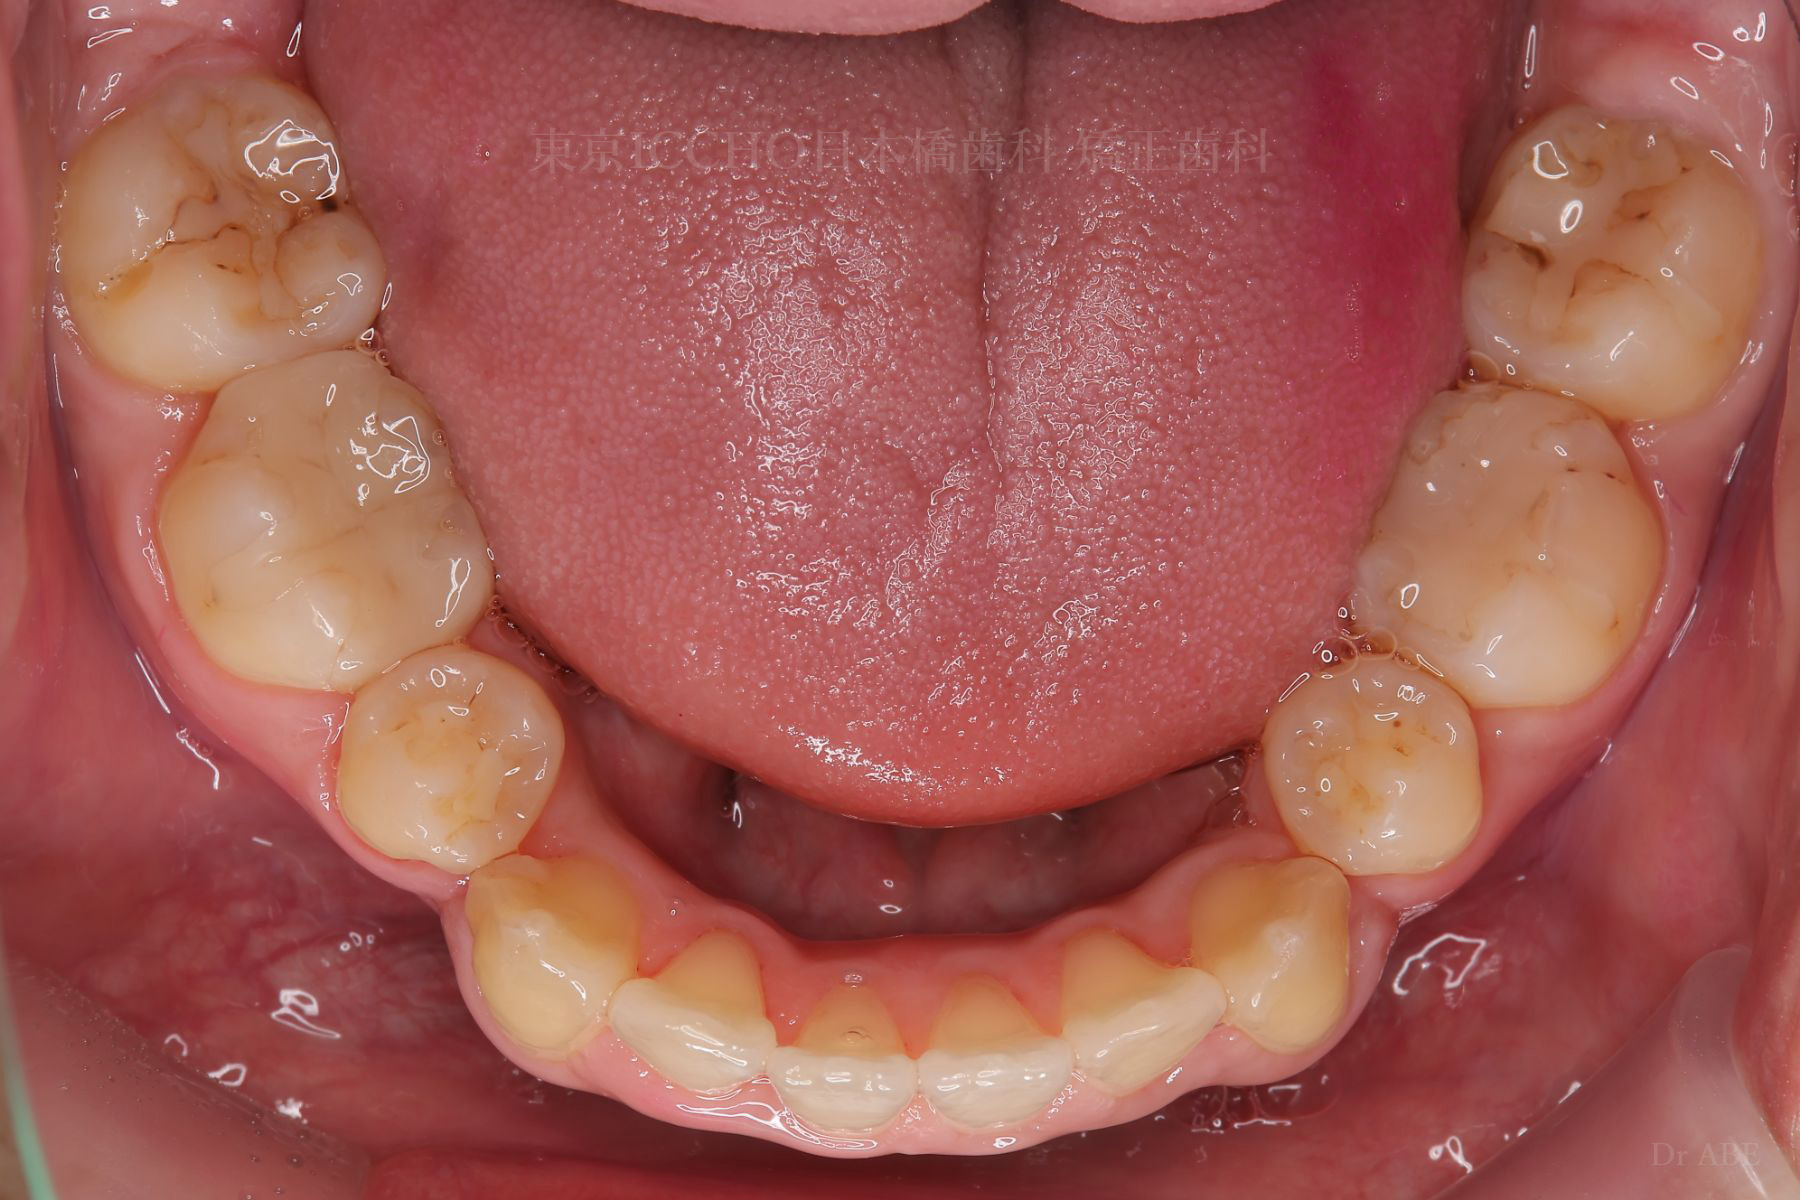

治療前

主訴 前歯が噛めないこと、出ているのを直したい。

治療内容 かみ合わせの不正と顎が小さいため、上下左右第一小臼歯4本の抜歯を行い前歯を後ろへ下げた。

また、前歯が噛まない状態のため、かみ合わせを少し下げて噛むように誘導し、全体的にかみ合わせとして機能的な矯正治療を行った。